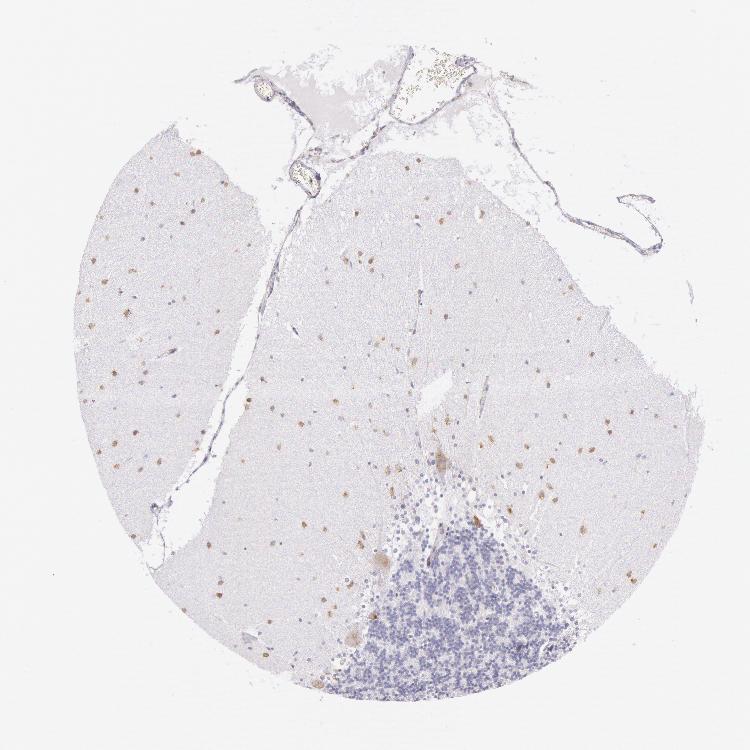

CEREBELLUM - Antibody stainingi

Antibody staining in the annotated cell types in the current human tissue is reported as not detected, low, medium, or high, based on conventional immunohistochemistry profiling in selected tissues. This score is based on the combination of the staining intensity and fraction of stained cells.

Each image is clickable and will lead to virtual microscopy that enables deeper exploration of all samples and also displays staining intensity scores, fraction scores and subcellular localization as well as patient and tissue information for each sample.

Antibody HPA001272

Purkinje cells Medium

Cells in granular layer Low

Cells in molecular layer High